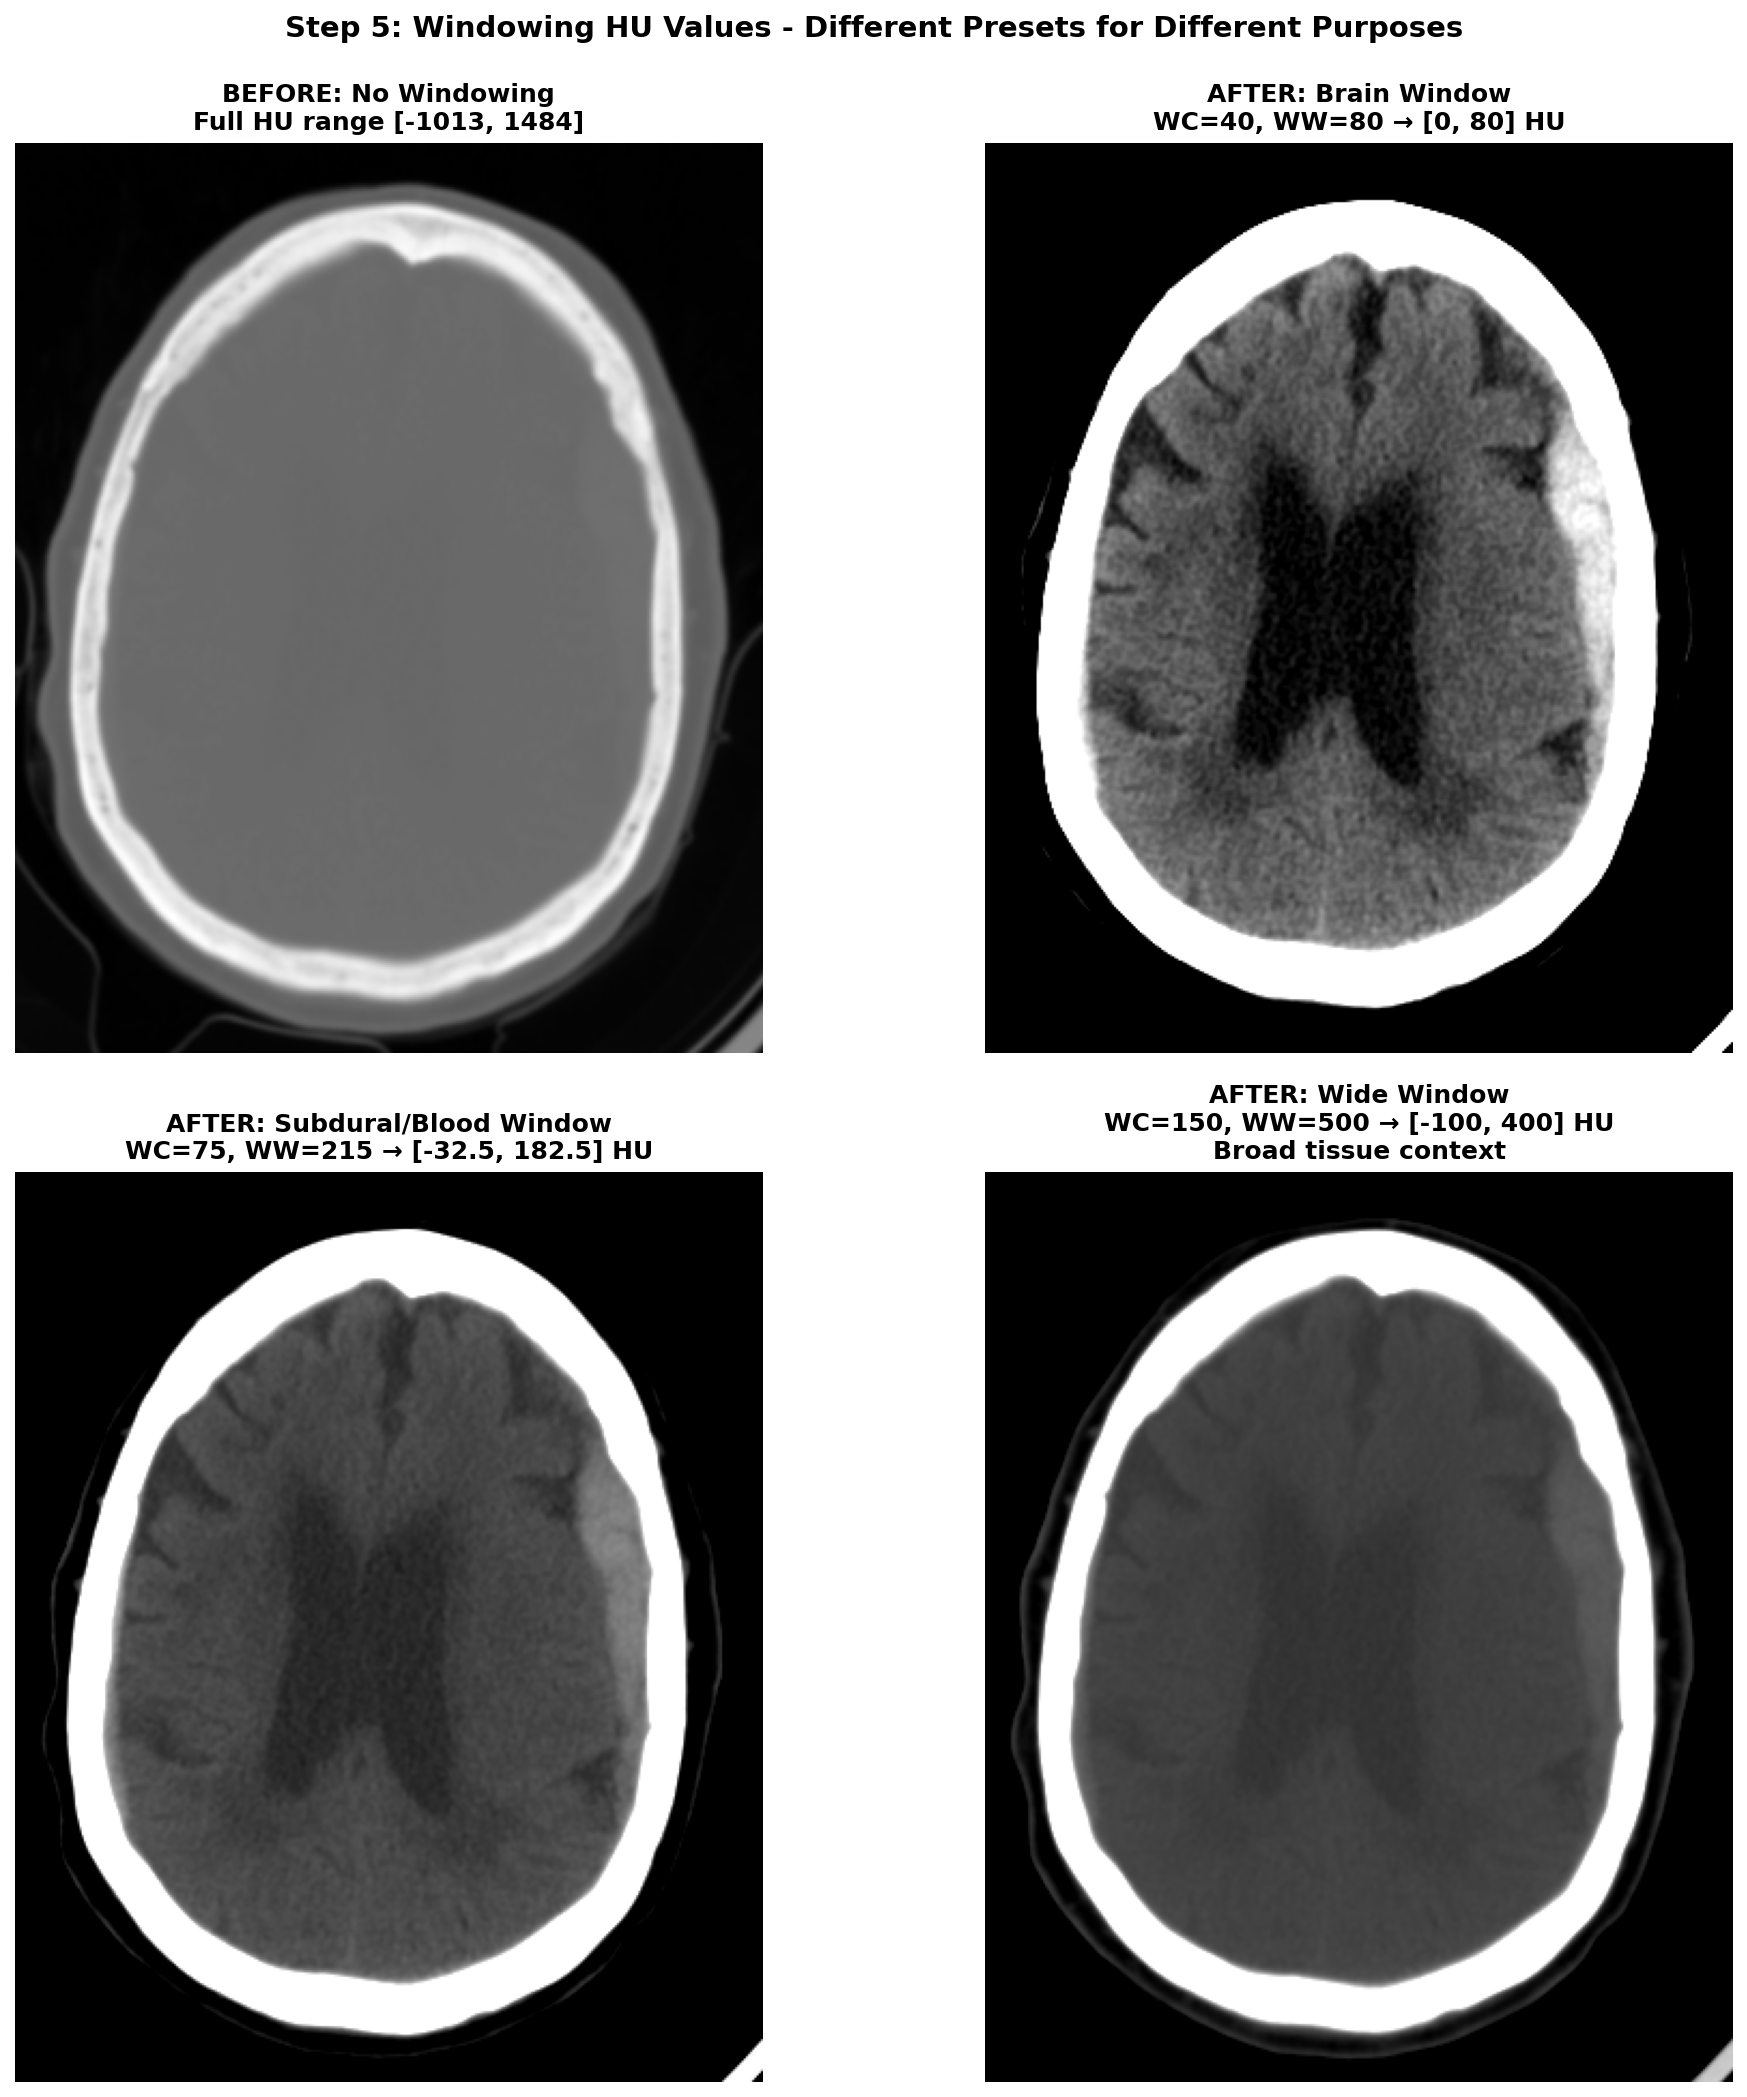

CT images require careful preprocessing before feeding into deep learning models. The process begins with Hounsfield Unit (HU) conversion, transforming raw DICOM pixel values into a standardized tissue density scale where water equals 0, air equals -1000, and dense bone reaches +1000. Next comes volume reconstruction, where slices must be correctly ordered along the z-axis —getting this wrong can scramble the anatomical sequence. Resampling standardizes voxel spacing to consistent resolution across different scanners and acquisition protocols. Brain cropping removes the skull, scalp, and scanner artifacts that add noise without contributing to stroke detection. Windowing restricts the HU range to highlight relevant anatomy; different window settings emphasize different tissue types, as shown in Figure 1 below. Finally, data augmentation through horizontal flips, small rotations, and intensity variations helps the model generalize beyond the training distribution.

Effect of windowing on CT visualization

To leverage ResNeXt's RGB pretrained weights on our grayscale CT data, I created a 3-channel input using different CT window settings, each emphasizing different tissue types and pathological features. The first channel used a brain window with center 40 HU and width 80 HU, optimized for viewing gray and white matter parenchyma. The second channel employed a subdural window with center 75 HU and width 215 HU, specifically enhanced for detecting blood and hemorrhage. The third channel used a wide window spanning -100 to 400 HU to provide broad tissue context including bones and soft tissues.

For each window, we define a center value and width, then calculate the minimum value as center minus half width and maximum value as center plus half width. We clip the image HU values to this range and normalize to the 0-1 interval. By stacking these three differently-windowed versions of the same slice, we create a pseudo-RGB input that mimics the structure of natural images while preserving clinically relevant information at different intensity scales.